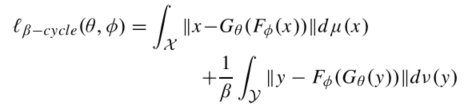

既然beta-VAE是在KL项增加beta,那我们自然就会想到在计算X和X’的距离时也添加一个参数beta。

也就是说,在计算循环损失(X和X’距离)时添加beta。

借鉴于beta-VAE,循环损失改写为如下形式: